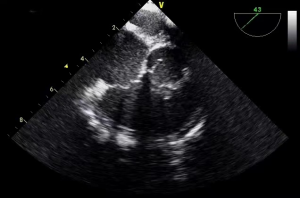

2.食道中段(图5):距门齿30cm-40cm,四腔观、五腔观、大动脉短轴观、左室长轴观、左室两腔心观、二尖瓣交界观、上下腔静脉观等。

食道中段四腔观和大动脉短轴观(图5)